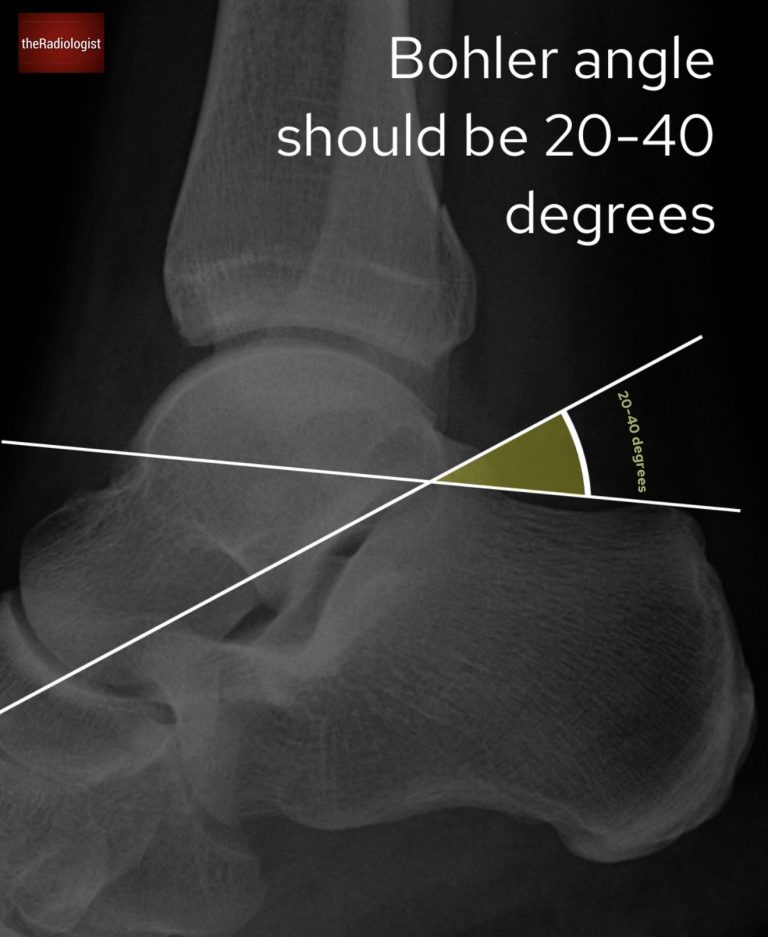

• Böhler angle: draw from the posterior tuberosity to the highest midpoint, then another line from the midpoint to anterior process. Measure the angle between the two lines: it should measure 20-40° (some places say less than 25 or 30°); <20° suggests a compression fracture.

Find the Böhler angle: draw from the posterior tuberosity to the highest midpoint, then another line from midpoint to anterior process. Find the angle between the two lines – this should be 20-40 degrees, any less could be a compression fracture of the calcaneus.